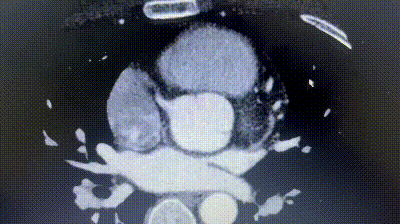

2. Koronar-CTA ergab einen anomalen Ursprung der linken Zirkumflex arterie (LCX) vom rechten Koronar sinus mit einem Verlauf zwischen der Aorta und dem linken Atrium.

3. Der Abstand zwischen der ASD und der aberra tanten LCX betrug nur etwa 6mm.